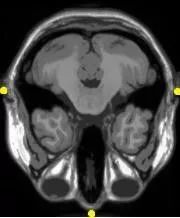

③Multi-modal Analysis: 多模态配准

多模配准常见于医学图像领域,故以多模医学图像配准为例。

由于医学成像设备可以提供关于患者不同信息不同形式的图像(计算机断层扫描CT,核磁共振MRI,正电子发射断层成像PET,功能核磁共振fMRI等)。

基于单种或多种模态图像的配准,可划分为单模态(Single-modality)和多模态(Multi-modality)。

Figure 1 MEG-MRI多模态配准